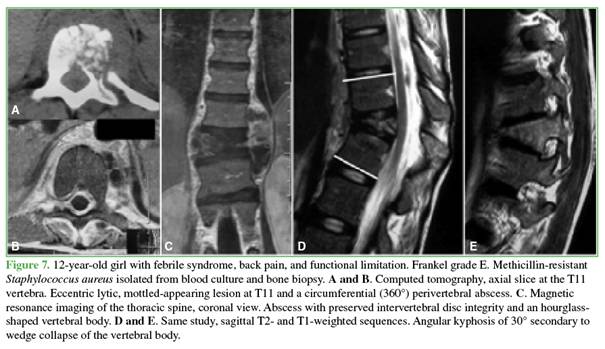

On computed tomography, bone lesions exhibited a lytic or mottled appearance, with asymmetric distribution and poorly defined margins. One patient developed angular kyphosis due to wedging of T11, which required delayed pedicle subtraction osteotomy (Figure 7).

Magnetic resonance imaging showed hypointense signal on T1-weighted sequences and hyperintense signal on T2-weighted and STIR sequences, with gadolinium enhancement. In patients with bone involvement and negative blood cultures, image-guided needle biopsies were performed: three percutaneous transpedicular biopsies, one transfacet biopsy, and one transoral biopsy. In two cases, no pathogen was identified; in two cases, S. aureus was isolated (1 MRSA and 2 MSSA). All specimens submitted for histopathological analysis were classified as acute osteomyelitis (Figures 8 and 9). According to protocol, all specimens were evaluated for tuberculosis (Figure 10).